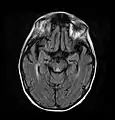

Axial MRI B=1000 DWI image showing hyperintense signal indicative of restricted diffusion in the mesial dorsal thalami